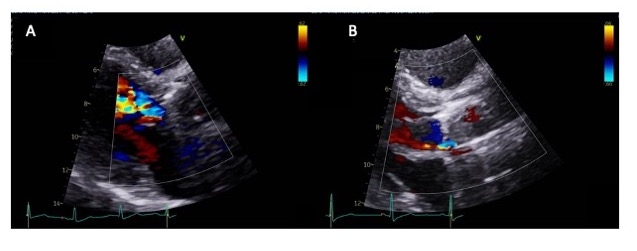

He was found to have SCAI-C cardiogenic shock, with exam notable for III/VI systolic crescendo-decrescendo and IV/IV decrescendo early diastolic murmurs, and absent mechanical click. Labs were notable for absolute eosinophils of 11.5 K/cu mm. On TTE, valve disks were poorly visualized. The mean gradient was 59mmHg and there was severe aortic insufficiency with preserved ventricular function. Due to concern for valvular obstruction, TEE was performed, revealing a well-seated valve with severe valvular regurgitation originating posteriorly and a reduction in systolic excursion of the disks. Valve fluoroscopy showed minimal movement of both discs suggesting thrombosis.